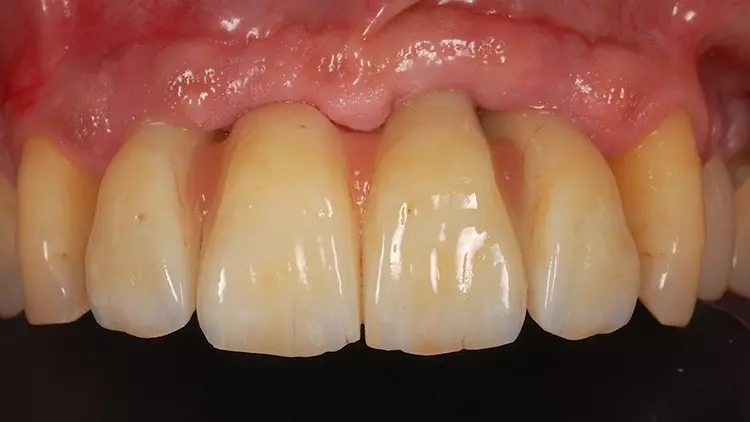

Als Interimsversorgung wurden herausnehmbare, klammerverankerte Prothesen aus Methylmethacrylat verwendet. Nach der dreimonatigen Einheilzeit erfolgten die Implantatfreilegung und die Versorgung mit Einheilkäppchen. Bei der Freilegung der Implantate und der Versorgung mit Einheilkäppchen sowie zum Zeitpunkt der Abformung mit den Abutments in situ lag eine reizlose klinische Situation ohne Anzeichen einer Entzündung im Implantatbereich vor (Abb. 4 und 5).

Nach weiteren vier Wochen wurden PS MultiPlus Abutments (BEGO Implant Systems GmbH & Co. KG) mit einem Platform Shift eingesetzt. Die MultiPlus Abutments wurden nach dem Prinzip „One Abutment, One Time“ direkt am Patienten verschraubt und nicht mehr entfernt. Die Interimsversorgung erfolgte über einen Zeitraum von weiteren zwei Monaten mittels verschraubter Provisorien aus metallverstärktem Komposit (LuxaCrown, DMG-Dental, Hamburg, Deutschland) (Abb. 6 und 7).